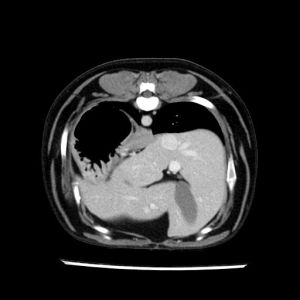

La lesione focale epatica , la ceus,la Tac e il chirurgo .